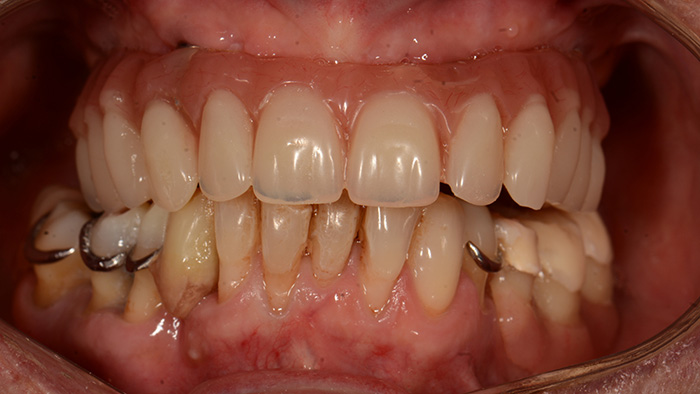

Fig. 12 : Une gouttière a été réalisée pour coller sur les dents 35, 36 et 37 du Stellite mandibulaire afin de retrouver une DVO et une occlusion équilibrée s’inscrivant dans une courbe de Spee et de Wilson idéale.

Fig. 13 : Des composites ont été réalisés en bouche au niveau de 44 et 45 pour retrouver des contacts lors de l’occlusion en intercuspidie maximale et en fonction de groupe lors de l’occlusion fonctionnelle droite.

Fig. 14 : Latéralité gauche en fonction de groupe.

Fig. 15 : Latéralité droite en fonction de groupe.

Nous retrouvons des AFMP droit et gauche symétriques, ce qui permettra une mastication unilatérale alternée.

Fig. 16 : Vue de profil

Fig. 17 : Aspect esthétique